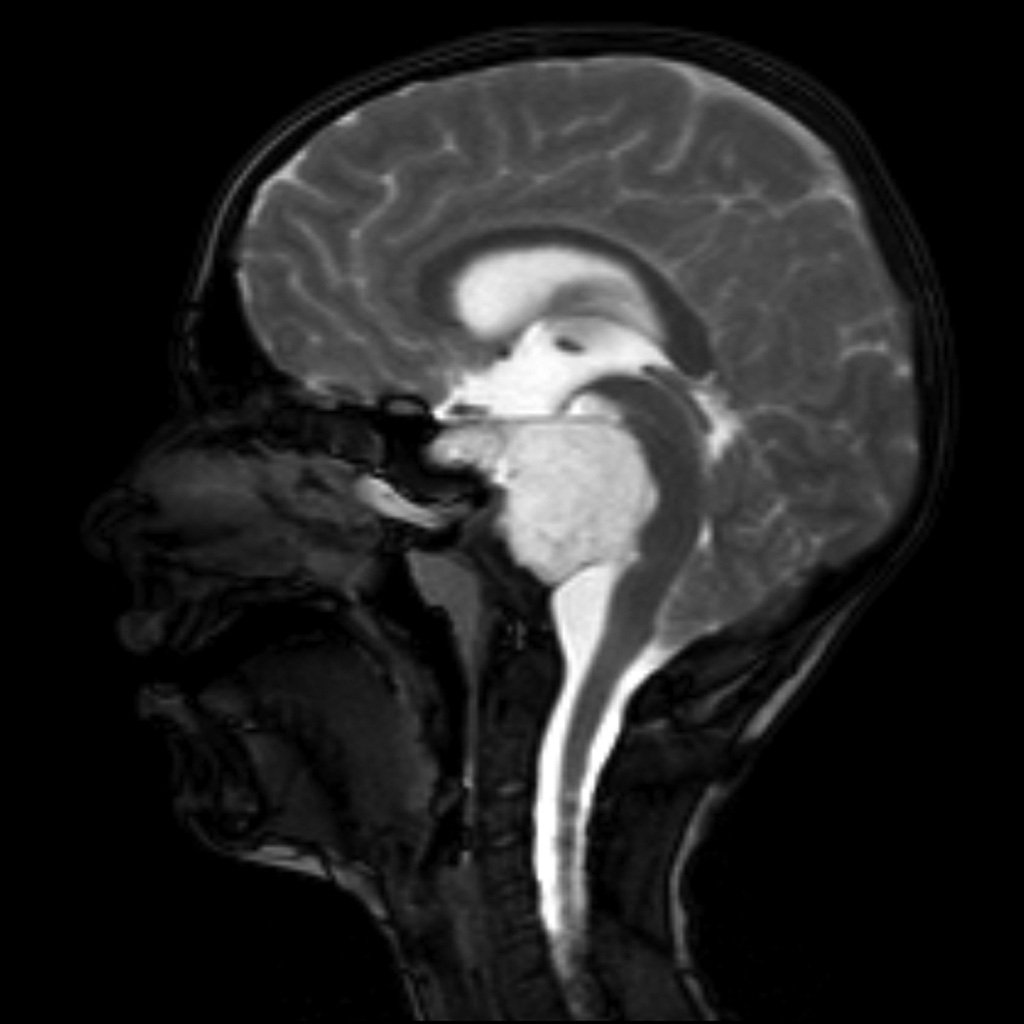

Chordoma

• Arise from notochord (therefore can arise anywhere from sacrum to sella)

• Locally aggressive bone mass

• Commonly present in spheno-occipital (near clivus) (young adults) or sacro-coccygeal (older adults) regions - typically in midline

• Thumb sign - the chordoma projects posteriorly causing mass effect on the anterior aspect of the pons as if your thumb was pushing it back

• Hyperattenuating and well circumscribed, may have intra-lesional calcifications (from erosion of local bone)

• MR:

• T1: low sign

• T2: high signal

• Typically septated

• T1 C+: heterogenous enhancement with honeycombing appearance